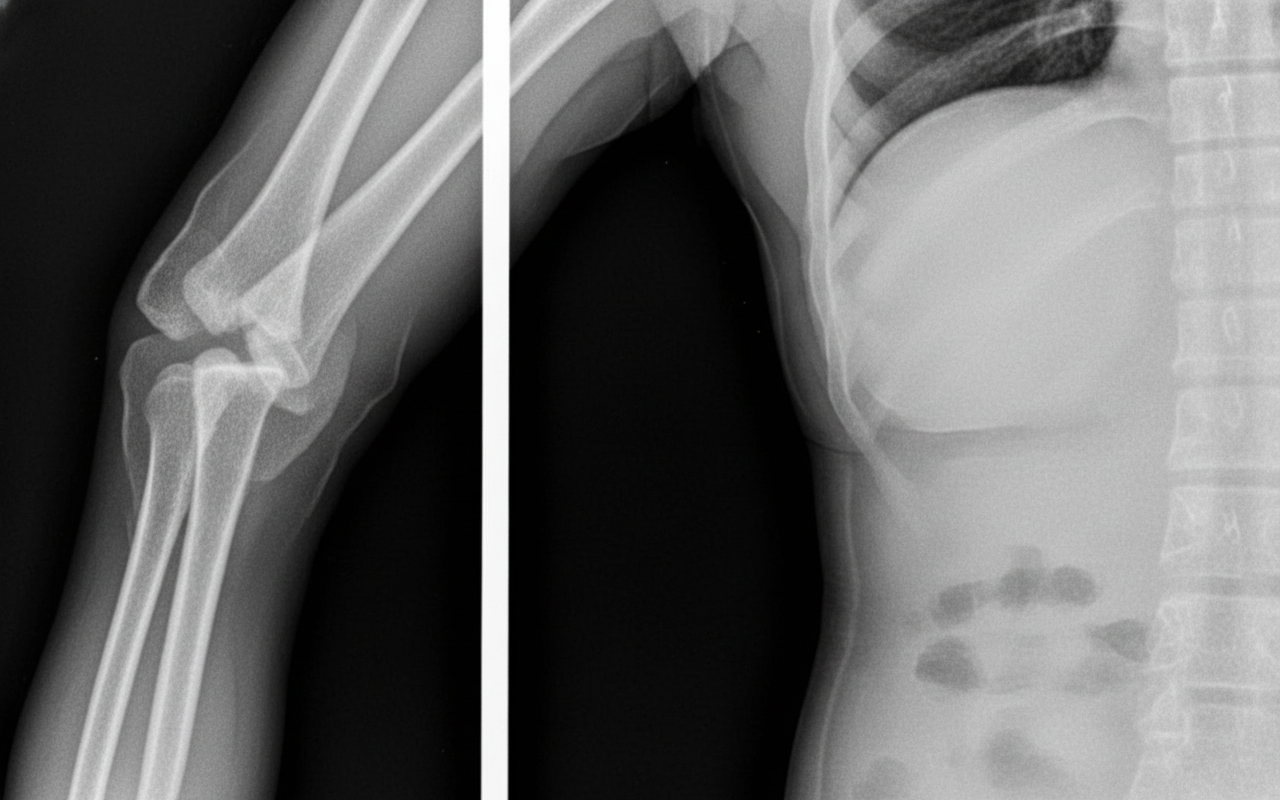

A 50-year-old male patient presented with a fracture as shown in the x-ray. On examination, there was paralysis of most of the intrinsic muscles of the hand and loss of sensation from the medial 1.5 palmar surface of fingers. Which of the following nerves arise from the same cord as the injured nerve, except?

Explanation: ***Thoracodorsal nerve*** - Arises from the **posterior cord** (C6-C8), not the medial cord like the injured **ulnar nerve**. - Innervates the **latissimus dorsi muscle** and does not share the same cord origin as the ulnar nerve. *Medial cutaneous nerve of arm* - Arises from the **medial cord** (C8-T1), same as the injured **ulnar nerve**. - Provides **sensory innervation** to the medial aspect of the arm and shares the medial cord origin. *Medial pectoral nerve* - Originates from the **medial cord** (C8-T1), identical to the **ulnar nerve** origin. - Innervates the **pectoralis minor** and part of **pectoralis major**, sharing the same cord as the ulnar nerve. *Medial branch of the median nerve* - The **median nerve** receives contributions from both **medial cord** (C8-T1) and lateral cord. - Its medial component arises from the **medial cord**, same as the **ulnar nerve** that causes the described symptoms.